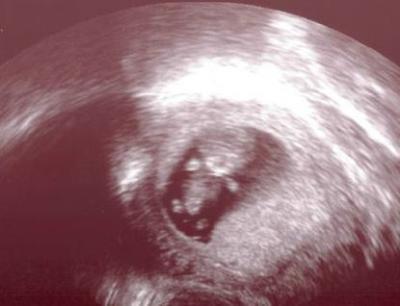

Hallo ihr Lieben, wir hatten am Montag unseren ersten richtigen Frauenarzttermin und waren soooo glücklich :) Es hat bei 9+6 fleißig gestrampelt :) In 2 Wochen geh ich zur NFM und kriege meinen Mutterpass *jippieh*

Bild zu Auch Termin gehabt - Forum für August - Mamis

Herzlichen Glückwunsch! Und das Bild ist ja echt gut geworden. Ich muss noch bis zum 26. warten. Da ist unsere NFM!

ein tolles Bildchen :-))) Alles Gute wünsche ich Dir weiterhin!!! LG EBLLA

Klasse Bildchen lg